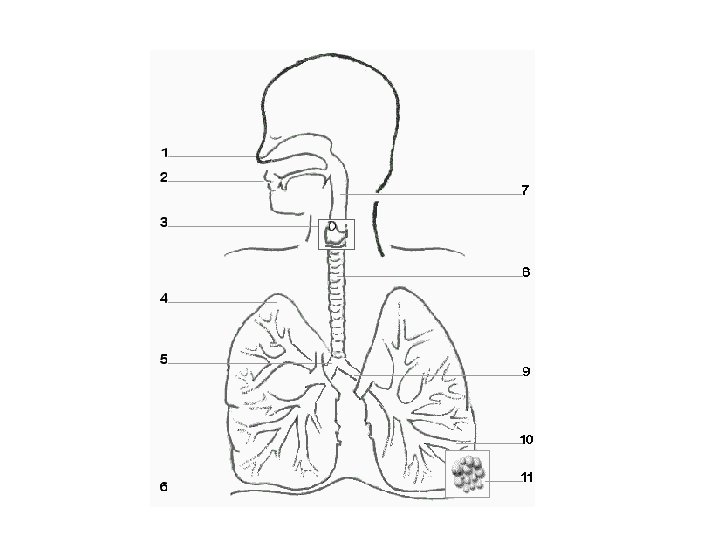

Human Respiratory System

Nasal Cavity Functions Filters Air Moistens Air Warms Air

Nasopharynx Links Pharynx & Nasal Cavity Explains why you can shoot milk out your nose

Pharynx: Back of Mouth Epiglottis covers larynx during swallowing to prevent food entering airway

Larynx: Voice Box Lined with vocal chords Control the pitch of voice

Trachea Also called windpipe Lined with cartilaginous rings And cilia to help clean the air

Bronchiole Tree

Alveolus Functional unit of resp. system Collectively, alveoli have large surface area: 70 m 2 (one side of a tennis court) Site of gas exchange Very thin walls Surrounded by pulmonary capillaries

Review: Write the Path of Oxygen Molecule From Outside of Body to Alveolus